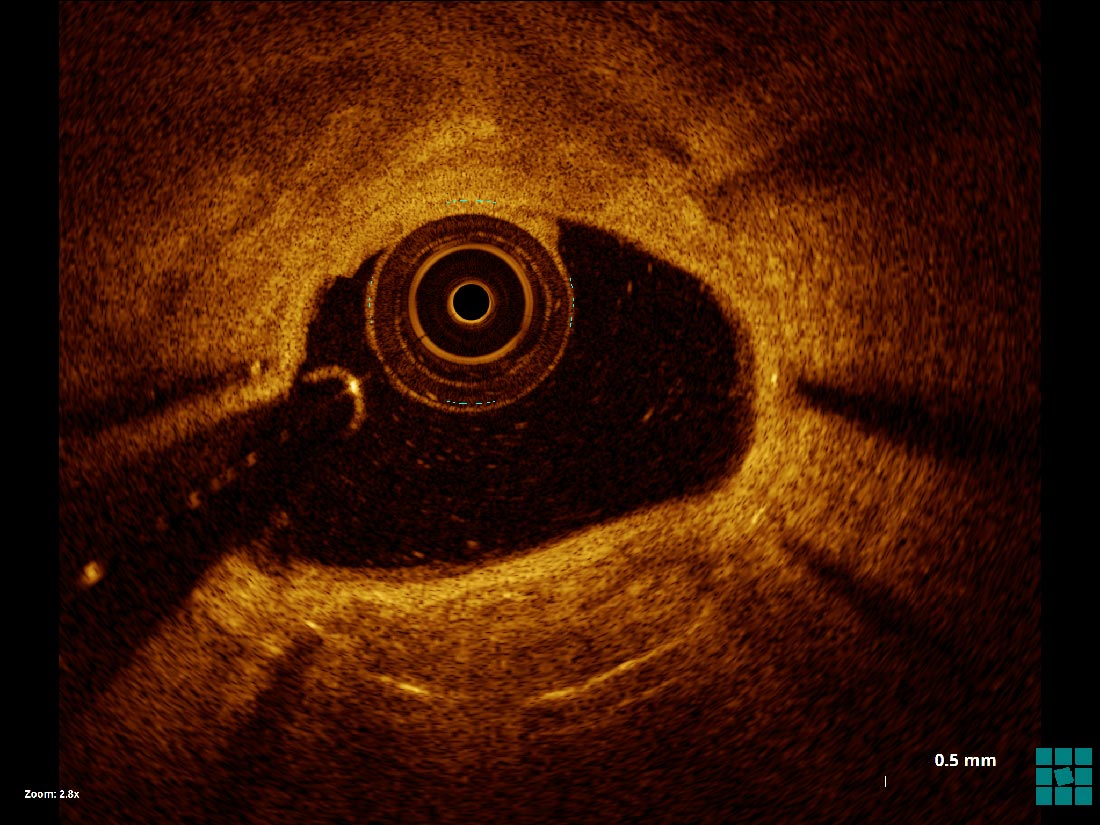

Center of Excellence in Optical Coherence Tomography (OCT)

University Hospitals has a well-established Center of Excellence in cardiovascular optical coherence tomography (OCT), which enables physicians to more expertly view tiny blood vessels in micro-meter resolution. In fact, our team helped develop OCT – pioneering research and clinical use of OCT since its investigational phase, and serving as the first U.S. site to teach doctors to perform OCT.

With OCT, our clinicians can view and measure important blood vessel characteristics otherwise invisible or difficult to observe with older imaging techniques. This advanced technology enables UH physicians to make more informed decisions regarding care and treatment by allowing them to:

neo calcification seen on OCT